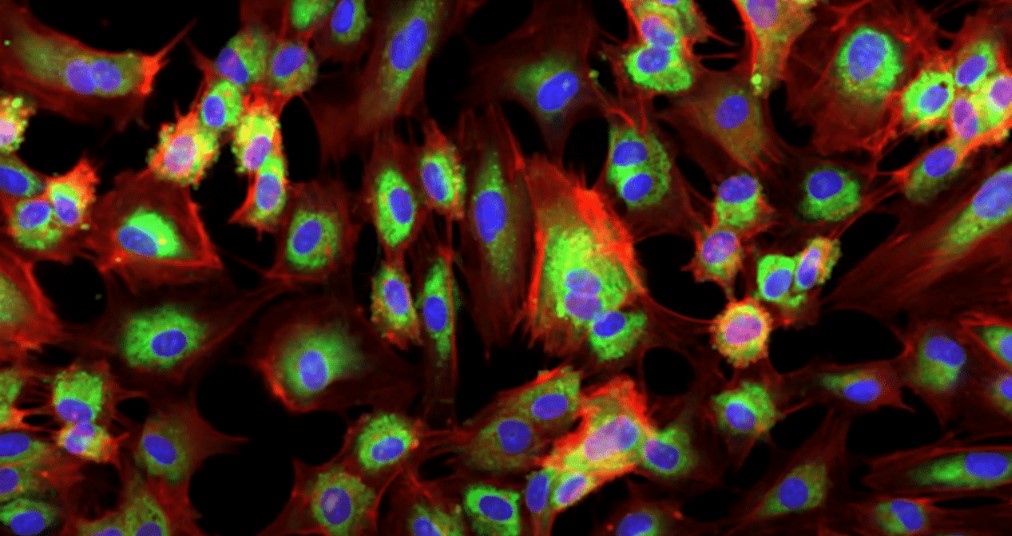

클라우드 API에는 저분자 생성을 위한 3가지 유형의 파운데이션 모델이 포함된다. 몰밈(MolMIM) 생성 화학 모델과 같이 엔비디아가 개발한 모델, 오픈폴드(OpenFold) 단백질 예측 AI와 같이 글로벌 연구팀이 개척하고 엔비디아가 선별하고 최적화한 오픈소스 모델, 세포 현미경 이미지 임베딩을 위한 리커션의 페놈-베타(Phenom-Beta)와 같이 엔비디아 파트너사가 개발한 독점 모델이 여기에 해당된다.

리커션은 바이오네모 클라우드 API를 통해 AI 모델을 제공하는 최초의 호스팅 파트너다. 세포 현미경 이미지에서 생물학적으로 유의미한 특징을 추출하는 비전 트랜스포머 모델인 페놈-베타가 그 주인공이다.

이 모델은 세포 기능에 대한 인사이트를 연구자에게 제공하고 세포가 신약 후보물질이나 유전공학에 어떻게 반응하는지 학습하는 데 도움을 줄 수 있다.

모델 성능을 평가하는 훈련 지표인 이미지 재구성에서 우수한 성능을 보인 페놈-베타 모델

페놈-베타는 엔비디아 DGX 슈퍼팟(DGX SuperPOD) 참조 아키텍처를 기반으로 하는 리커션의 BioHive-1 슈퍼컴퓨터를 사용해 공개적으로 사용 가능한 생물학적 이미지의 RxRx3 데이터셋을 훈련했다.